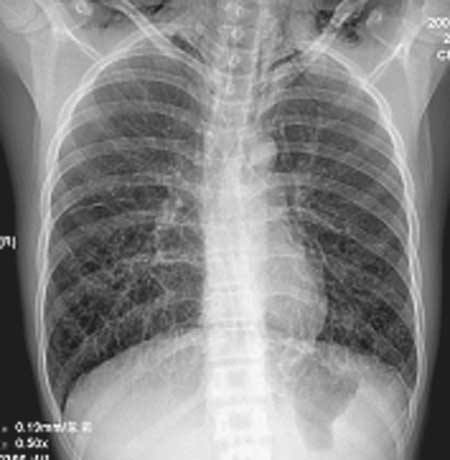

x:双肺中下野多发囊状卷发状影,壁模糊,无液平,双肺纹理强,-------印象:先天支扩并感染.

侧位胸廓前后径明显变小,心脏狭长.-------------扁平胸?--------需结合临床.

颈肩部皮下软组织低密度影,-----------考虑软组织重叠影,不排除皮下气肿,-----请提供病史.

双肺纹理粗乱,双下肺见网囊小点结影,膈肌低位,颈部见皮下气肿征,侧位可疑纵隔气肿。男性,16岁,无相关病史可考虑1间质性肺炎。2慢支炎或支气管哮喘。3支扩及其他待排请提供病史

正位片摄片方式不对,肩胛骨未拉出,但从片上看就是两下肺透光度增强,考虑支扩可能性较大,侧位片不正,纵隔前缘考虑对侧胸廓影,因为两片放大率不知怎样,就从片子上看有直背综合征表现。

王某某,男,16岁,既往无经常咳嗽、咳痰、胸闷、发热史,活动与同龄儿童相似,三月前突感胸、颈前痛、无喘憋,查体胸骨上皮下气肿,双肺呼吸音对称。胸部dr及ct示纵隔气肿,双肺囊肿。近两月反复出现胸痛、喘憋,无发热、黄痰及痰血,呼吸音减低,胸部dr示双侧自发性(张力性)气胸,胸腔闭式引流治愈。频繁发作,左侧引流两次,右侧引流三次。

1.诊断考虑先天性肺囊肿(囊性肺),自发性、张力性气胸,鉴别支气管扩张,先天性囊性腺瘤样畸形等

从上述x线片、ct片看,先考虑先天性肺囊肿(囊性肺),伴气胸、纵隔积气、皮下积气;先天性囊性腺瘤样畸形,一般中叶很少累及.

先考虑先天性肺囊肿(囊性肺),伴气胸、纵隔积气、皮下积气,胸水.先天性囊性腺瘤样畸形